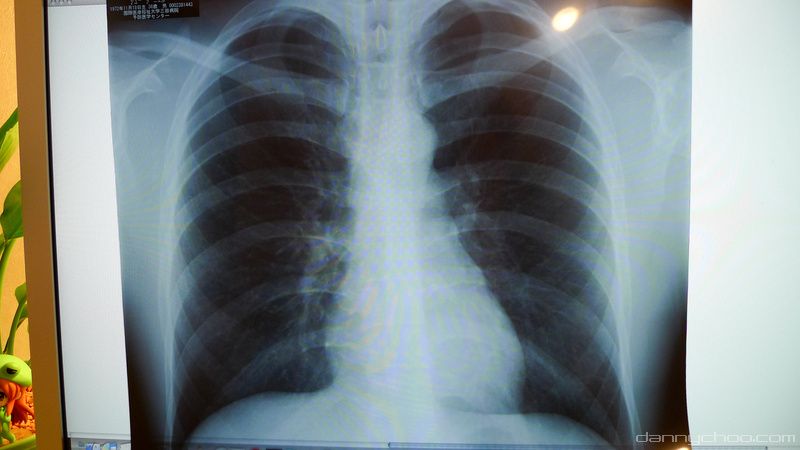

And my chest scans. A report will come back to me after a few weeks so have not been given the lowdown on these scans yet.